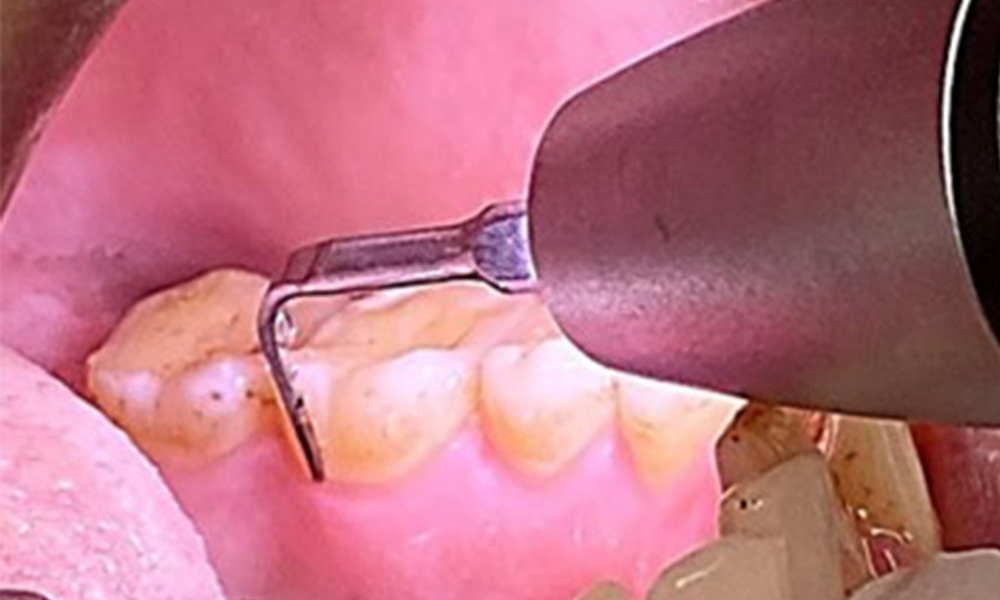

Use of a piezo-driven ultrasonic device in the lingual area near 36 (Proxeo Ultra, W&H, shown here)

Fig. 10 Use of a piezo-driven ultrasonic device in the lingual area near 36 (Proxeo Ultra, W&H, shown here), © Dr R. Krapf

The objective would be to control disease risk by removing supragingival and subgingival biofilm. The instruments can be selected based on patient needs. First, calculus and any concretions must be removed using ultrasonic and/or manual instruments (Fig. 10).